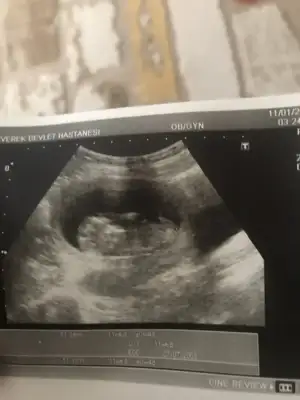

Maalesef elimde ayrı günlerde çekilmiş iki usg tek var cuma günü gideceğim doktora bakalım okursa onu paylaşırım.Başka usg varmı 11 yada 12 hafta kız gibi ama emin olamıyorum

Net degil usg gördügüm nub ise erkek gibi başka varsa usg 11 yada 12 hafta paylaşın bu usg kaç haftalıkbanada tahminde bulunurmusunuz rica etsem

15 hafta usg nubu dik görünüyor sanki erkek gibi 11yada 12 hafta usg varmıSizce nedir?